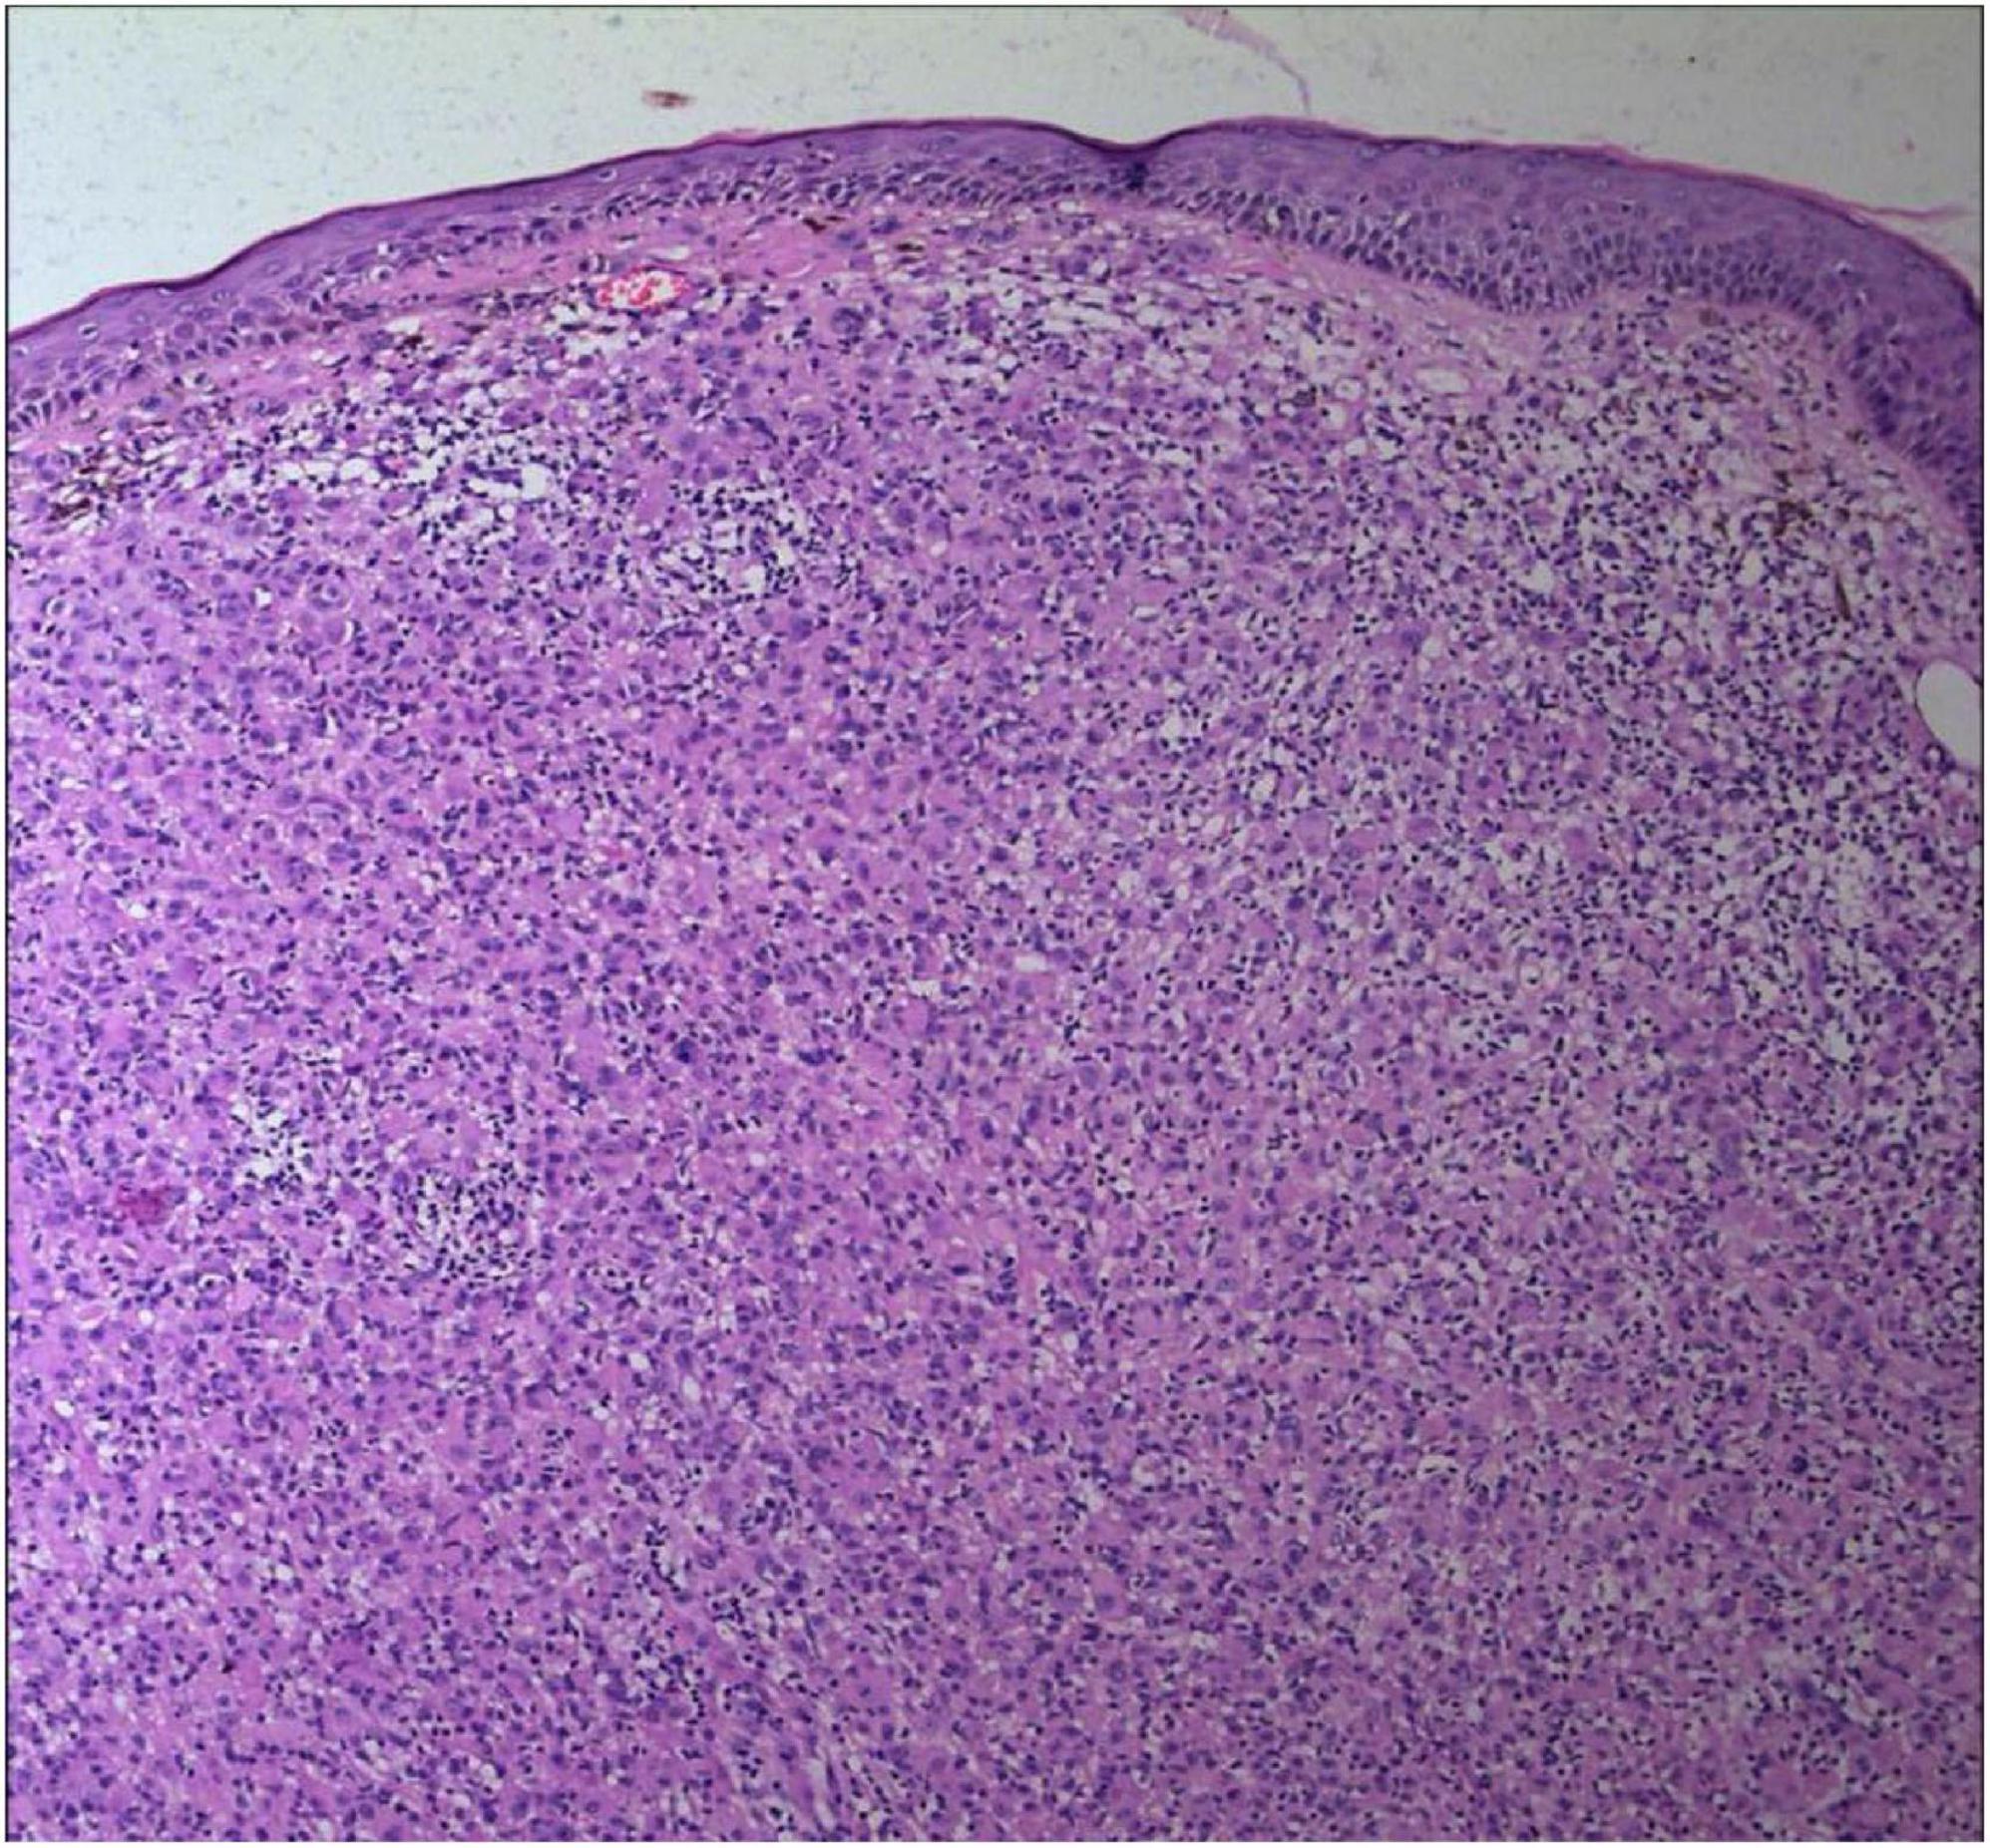

FIGURE 3

The tumor cells were polygonal, either round or oval, which had abundant cytoplasm filled with eosinophilic granules, and were stained pale pink. The nuclei were small, hyperchromatic and centered, with few mitotic figures, and multiple nuclei were observed in some tumor cells (Hematoxylin and Eosin Stain, × 200).

No abnormalities were found upon routine blood and urine tests, coagulation function test and syphilis/HIV screening. Chest X-ray and abdominal B-ultrasound also revealed no abnormalities. Cutaneous histopathology: epidermal processes disappeared, and the dermis was diffusely infiltrated by substantial tumor cells that were in the nested or clumpy form. These polygonal tumor cells were round or oval, which had abundant cytoplasm filled with eosinophilic granules, and were stained pale pink. The cellular nuclei were small, hyperchromatic and centered, with few mitotic figures, and multiple nuclei were observed in some tumor cells. Immunohistochemistry: S-100 (+), CD56 (−), NSE (−), vimentin (+), CD68 (+), Ki-67 (+), cell proportion: 5%, p53 (−), SAM (+−). CK (−), calponin (−), CD163 (−), desmin (−), CD34 (−), CD45 (−), CD30 (−), SMA (1A4) (−), ALK (−), HMB45 (−), melan-A (−).

2.3.2 The histopathological features

The dermis was diffusely infiltrated by substantial tumor cells that were in the nested or clumpy form. These polygonal tumor cells were round or oval, which had abundant cytoplasm filled with eosinophilic granules.